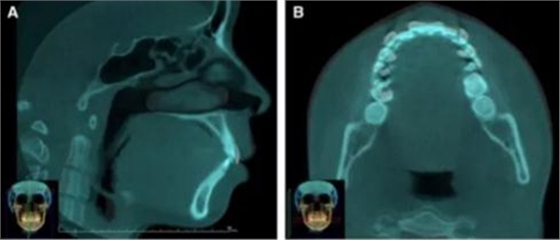

頭側(cè)分析提示為骨性安氏II類(ANB,8.4°;Wits,3.6mm),高角(SN-MP,44.9°),上頜切牙略舌傾(U1-SN,96.2°),下頜切牙略舌傾(IMPA,88。3°)(圖2;表)